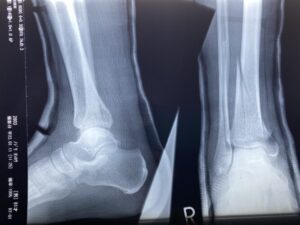

二分靱帯損傷・前距腓靭帯損傷・腓骨下端部骨折・第5中足骨骨折後に行うリハ…

骨折・脱臼